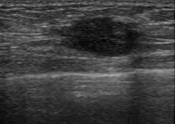

¶ÇÇÑ ¼­¾ç ¿©¼ºÀÇ À¯¹æÀº Á¶Á÷ÀÌ ¹°··¹°··ÇÕ´Ï´Ù.±×·¯³ª Çѱ¹ ¿©¼ºÀÇ À¯¹æ¿¡´Â ´Ü´ÜÇÑ À¯¼±Á¶Á÷ÀÌ ¸¹½À´Ï´Ù.±×·¡¼­ 'Ä¡¹ÐÀ¯¹æ'À̶ó ºÎ¸¨´Ï´Ù. Ä¡¹Ð À¯¹æÀϼö·Ï ¾Ï¿¡ Àß °É¸®°í Á¶±â ¹ß°ßÀÌ ¾î·Æ´Ù´Â ¿¬±¸°á°ú°¡ ³ª¿À°í ÀÖ½À´Ï´Ù.